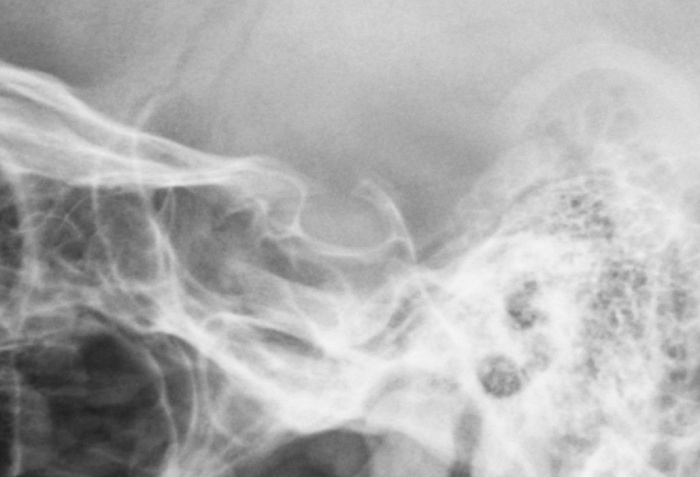

Рентгенография турецкого седла Рентгенография турецкого седла

Рентгенография турецкого седла

Рентген турецкого седла - важный метод исследования, который позволяет получить детальное изображение области турецкого седла головного мозга.